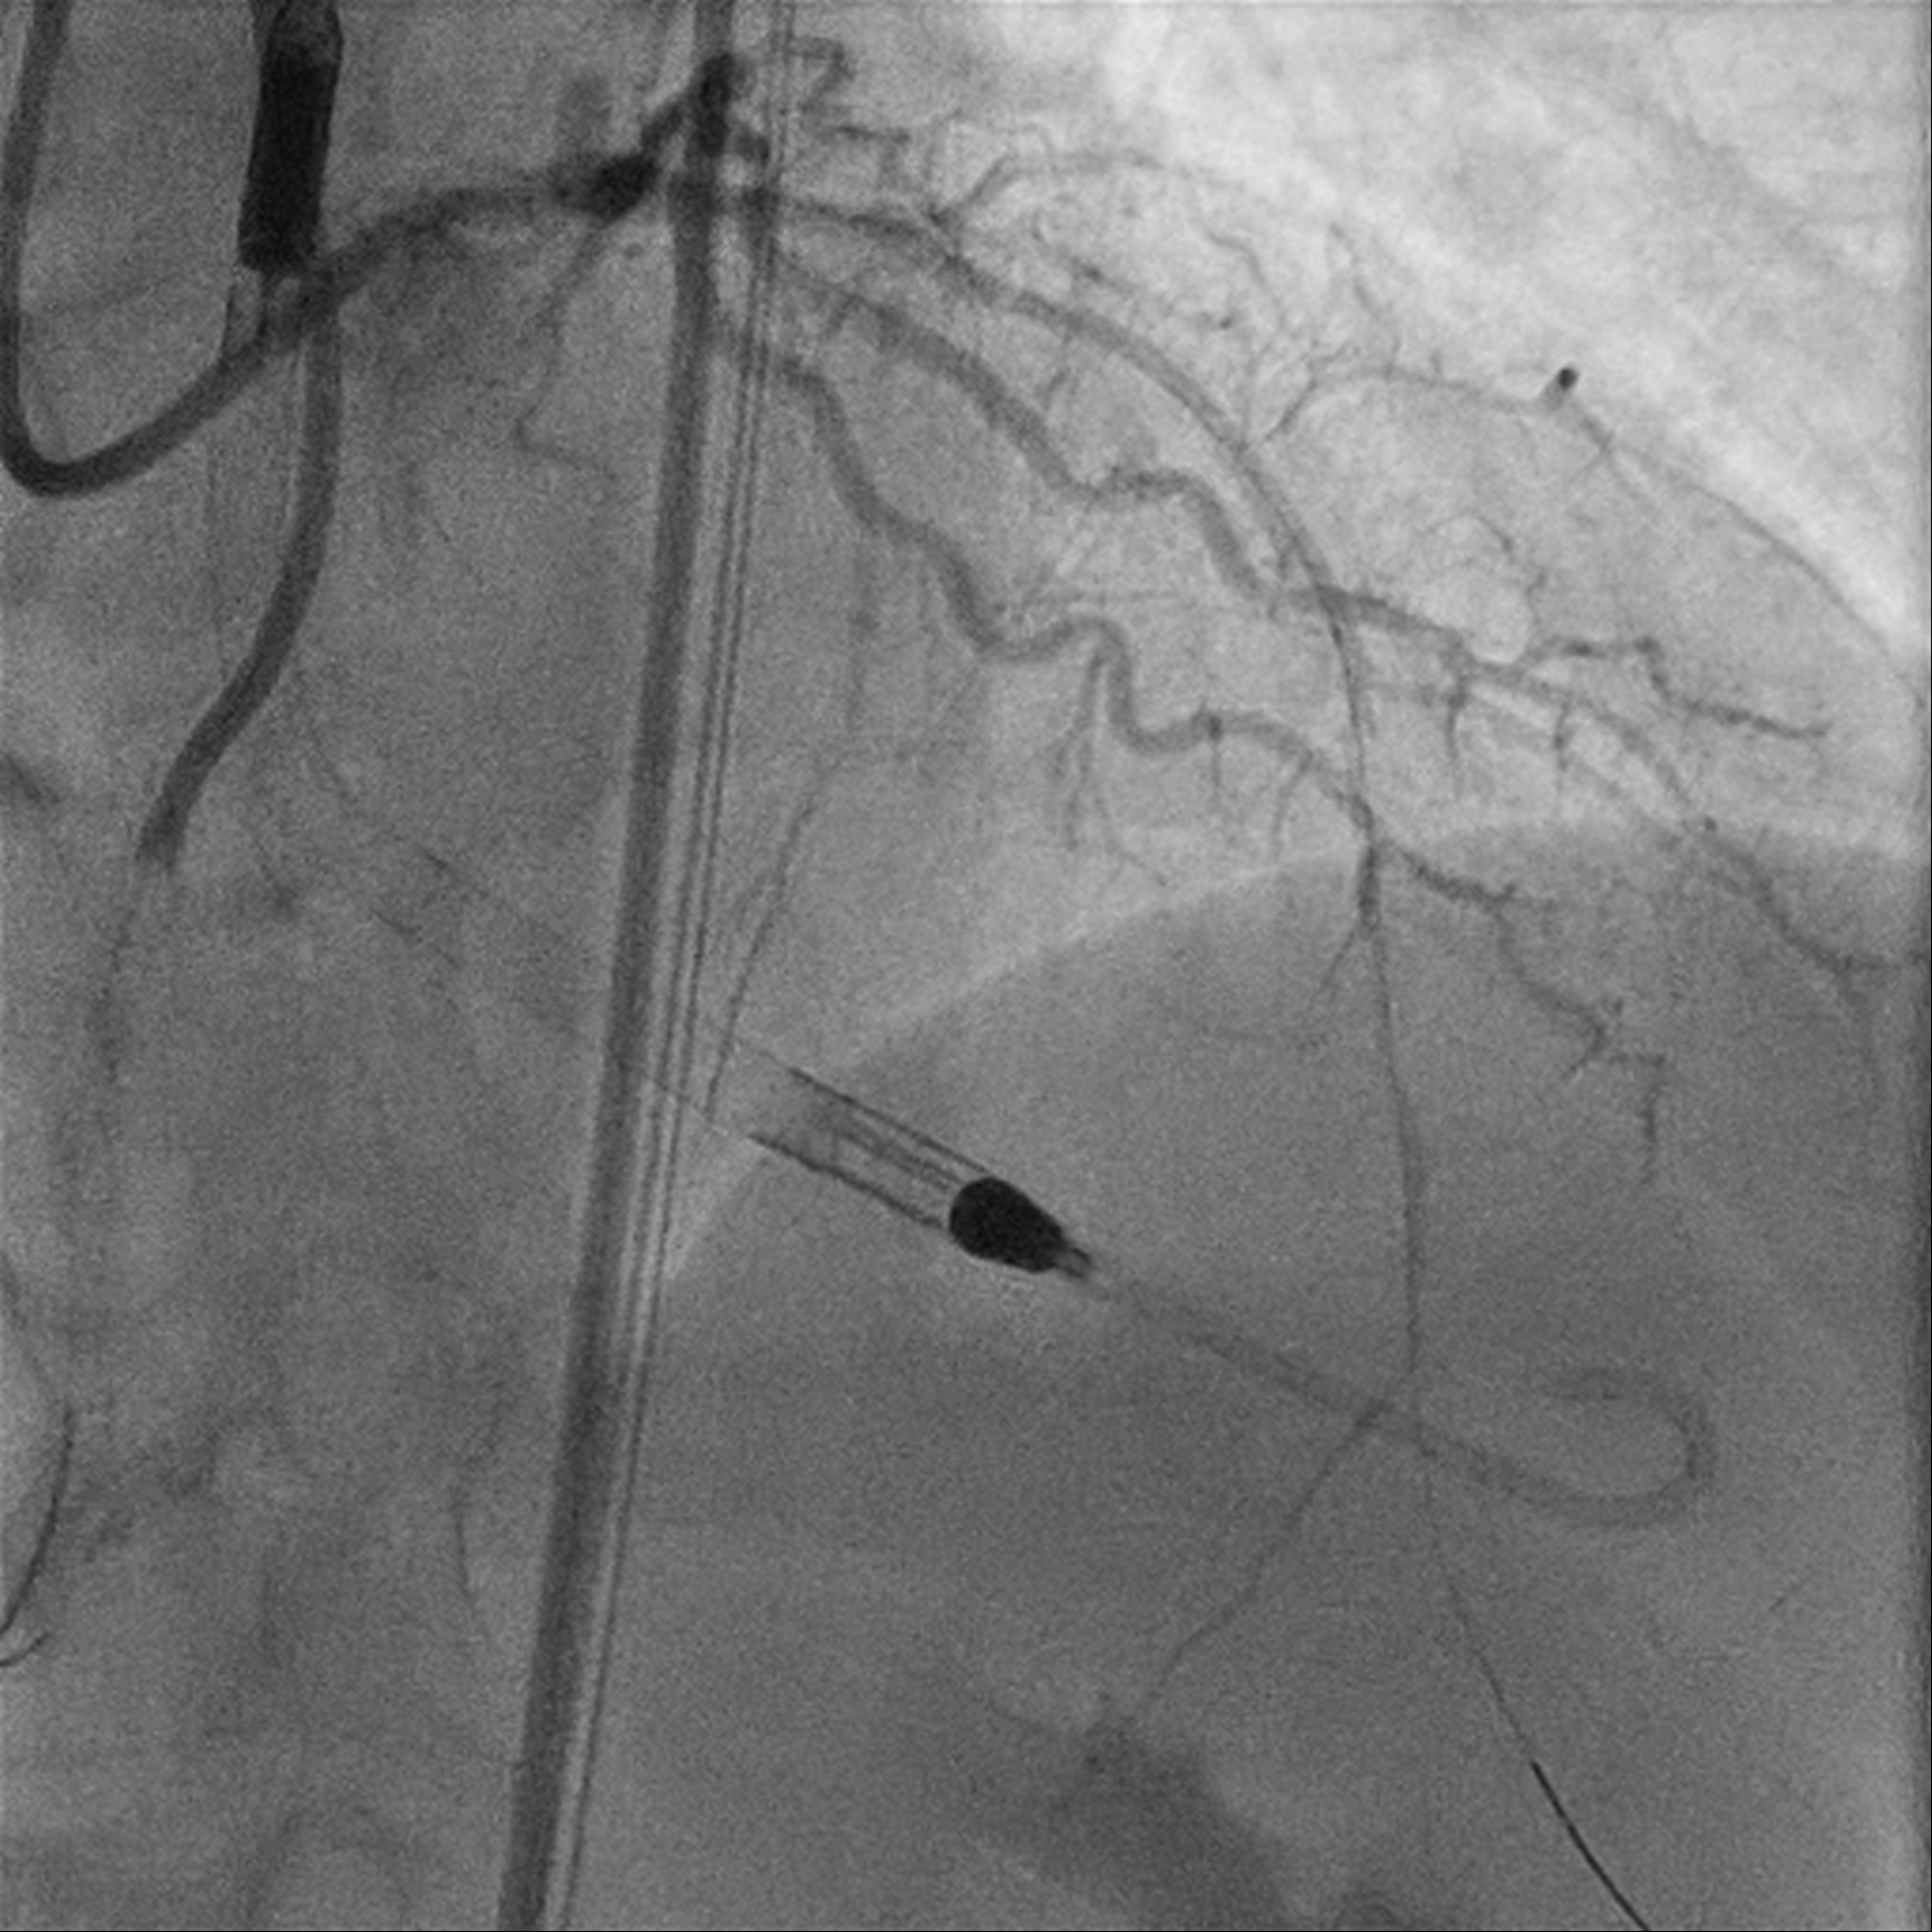

Procedural Step

Upfront MCS support using Impella CP via R CFA. Eccentric calcified plaque over m-dRCA, fibrofatty atheroma elsewhere. Initially plan for DCB over dRCA, however developed distal dissection, pRCA to PDA stented with total of 4 stents. Impinged PL branch ostium after stenting, branch rewired then POBA. Final IVUS and angiography shows good results. mLAD CTO crossed with Gaia 2 but Caravel unable to cross. CTO segment then dilated with semi compliant 0.85mm balloon then 1.5mm balloons. IVUS confirmed wire within true lumen throughout with long segments of calcific lesion. Rotational atherectomy with 1.5mm burr for 7 passes then further predilation with NC 2.75mm balloon. However, complicated with no reflow afterwards. Prolonged inflation of long segment compliant balloon followed by adenosine injection improved flow. IVUS showed calcium fracture but inadequate luminal gain, decided for IVL. Total of 8 cycles using 2.5mm shockwave, post IVUS showed improved luminal gain with more calcium cracking. DCB to m-dLAD afterwards for calcified diffuse disease. However developed no reflow after Paclitaxel-coated DCB which complicated with 1 episode of VT requiring cardioversion. Repeated adenosine injection improved flow, patient stabilized.